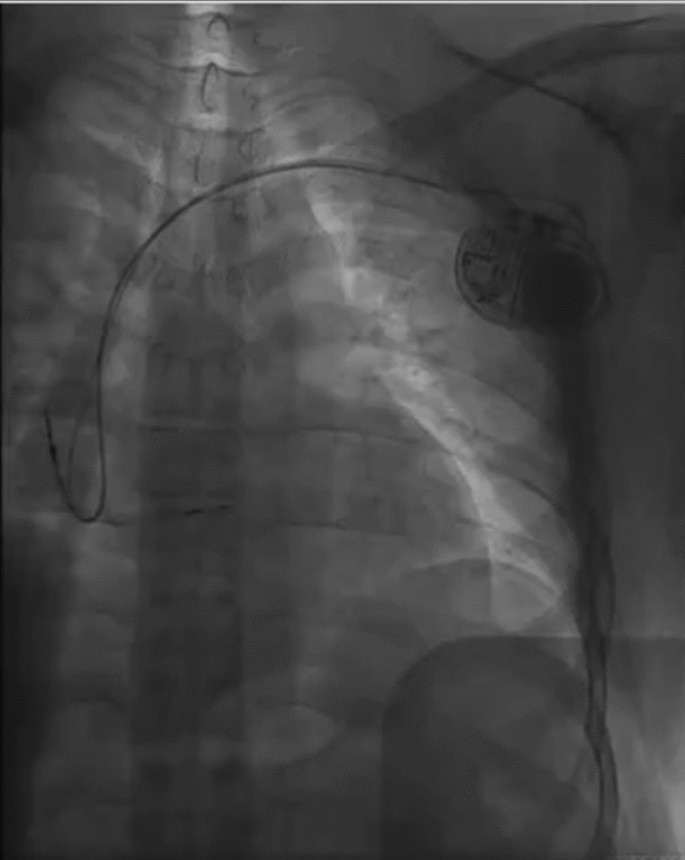

The standard group The patient was positioned supine with ECG monitoring and multi-conductive physiological apparatus connected. The 3830 lead and the C315His sheath are used as the pacing lead and the delivery catheter. Under the right anterior oblique 30° (RAO 30°) fluoroscopic view, a Model 3830 pacing lead (Medtronic) was placed at the atrioventricular node to determine the optimal location of HBP lead deployment. At this location the His potential was recorded, or HB captured by unipolar pace mapping (Fig. 1). The lead was fixed at a satisfactory position with respect to pacing parameters.

Final lead position in the fluoroscopic image in the standard group.